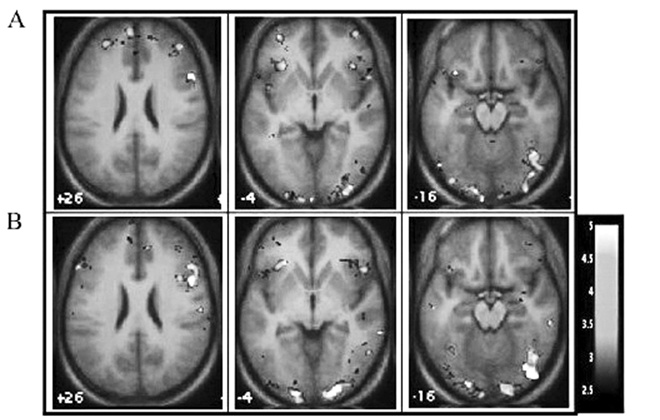

Затем с помощью фМРТ она изучала то, что при этом происходило в их мозгу.

Обнаруженное ею оказалось весьма необычным и интересным. У тех, кто при тестировании выдал высокие результаты, активность мозжечковой миндалины снижалась по сравнению с теми, чьи результаты были ниже (что вполне согласуется с дефицитом в обработке эмоций по «горячим следам»), зато активность и зрительной, и дорсолатеральной зон префронтальной коры – повышалась.

Это, как отмечают Гордон с коллегами, указывает на то, что «участники с высокими результатами, дабы выполнить поставленную перед ними задачу распознавания эмоций, задействовали области, связанные с восприятием и познанием» (рис. 7.1).

Правая часть дорсолатеральной префронтальной коры

Правая часть нижней лобной извилины

Зрительная зона

Рис. 7.1. Активность в зависимости от уровня оксигенации крови во время распознавания эмоций относительно базового уровня. (A) Участники, показавшие результаты ниже средних на PPL. (B) Участники, показавшие результаты выше средних на PPL. Картинки, представленные в неврологической ориентации: левая часть картинки соответствует левому полушарию мозга (по Гордон и др., 2004)